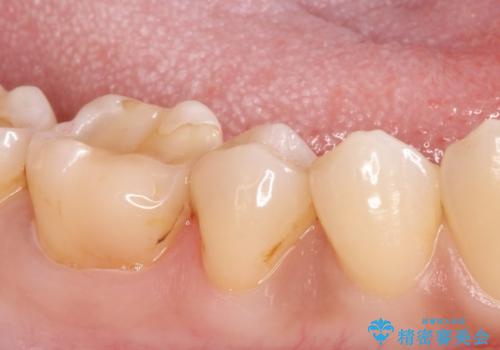

- 歯が欠けて、そこに食べ物が詰まるとのことで来院されました。

虫歯が大きく進行していました。

顕微鏡下で丁寧に虫歯を取り除き、セラミックインレーによる修復治療を行いました。